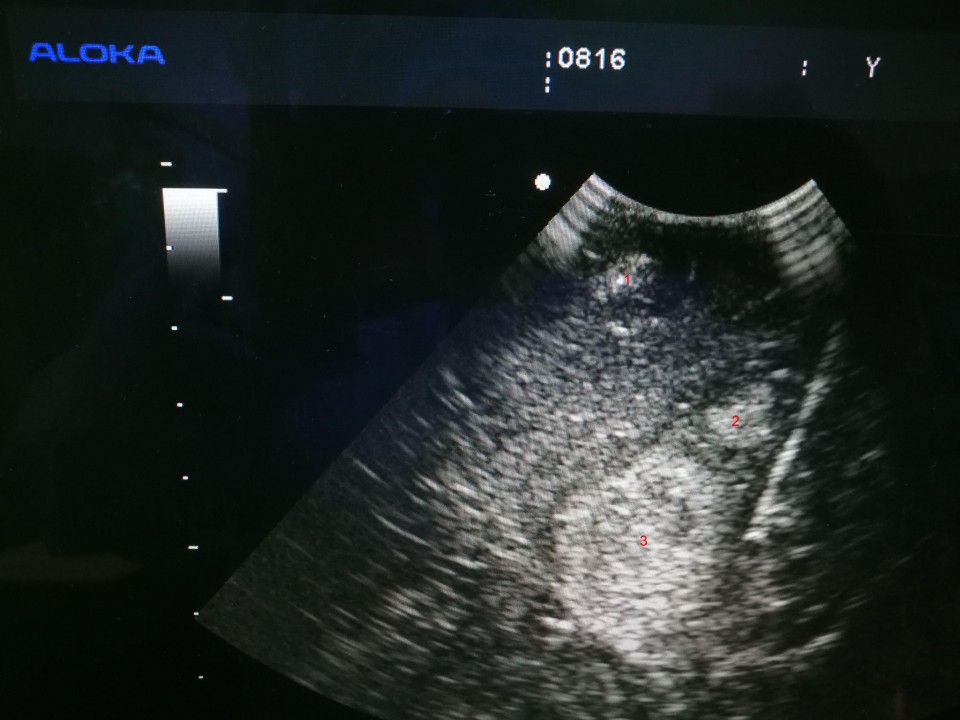

术中B超引导证实肿瘤所在位置

患者,女,51岁,系头痛头晕1月余”入院,入院后完善相关检查,专科检查:神清,精神差,双瞳孔等大等圆,光敏(+),左侧肢体肌力IV级别,右侧肢体肌力正常,余检未见明显异常。头颅MRI检查示:颅内多发性肿瘤,考虑转移瘤可能。遂行PET-CT检查未发现颅外原发性病灶。完善术前常规相关检查,未见明显手术禁忌后,于全麻下圆满完成术中B超引导下一次性切除颅内多发肿瘤手术,在经过家属及护理部的精心护理,患者术后恢复良好。

王斌指出,颅内深部多发肿瘤是神经外科治疗难题,因其位置深、病灶多、解剖关系复杂,常规手术造瘘难以完全探及肿瘤且对脑组织损伤大,容易造成患者功能缺失,致使患者难以接受手术。因此,如何更有效的切除脑肿瘤,并且同时尽量减少脑组织损伤,保留患者功能就成为了神经外科研究的热点与焦点。我院神经外科一病区王斌主任团队在开颅显微切除肿瘤的基础上进一步改良创新开展了术中B超引导下一次性切除颅内多发肿瘤术,成功的为这名患者实施了脑肿瘤完全切除,术后患者功能完全正常。(王斌 洪文明)